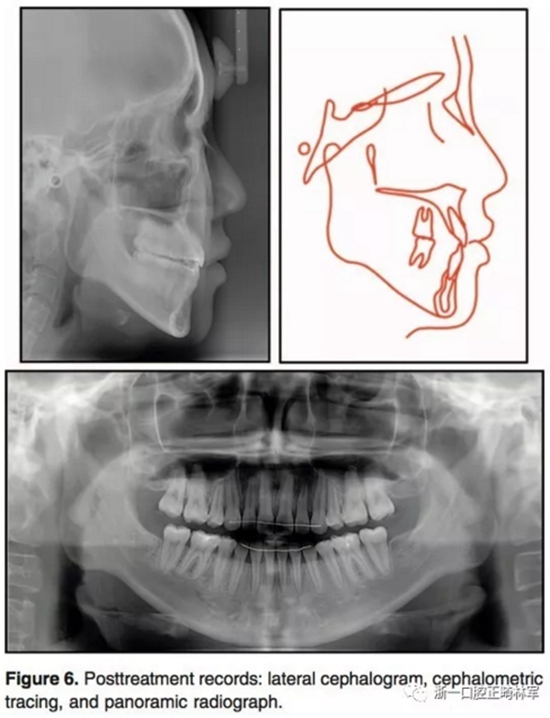

治療后結(jié)果示,治療目標達成。側(cè)貌改善。唇可以完全閉合,獲得了美學(xué)微笑(圖5)。全景示間隙關(guān)閉,牙根平行度可,未見明顯吸收。側(cè)位片分析和重疊像分析示上前后牙分別壓入2.8mm和1.9mm。下前后牙分別壓入4.2mm和1.4mm。上下頜前牙用最大支抗內(nèi)收。雙牙弓壓入后,下頜發(fā)生了逆時針旋轉(zhuǎn)(2.1°)??和頦前點前移(3mm)。

6.jpg

7.jpg

8.jpg